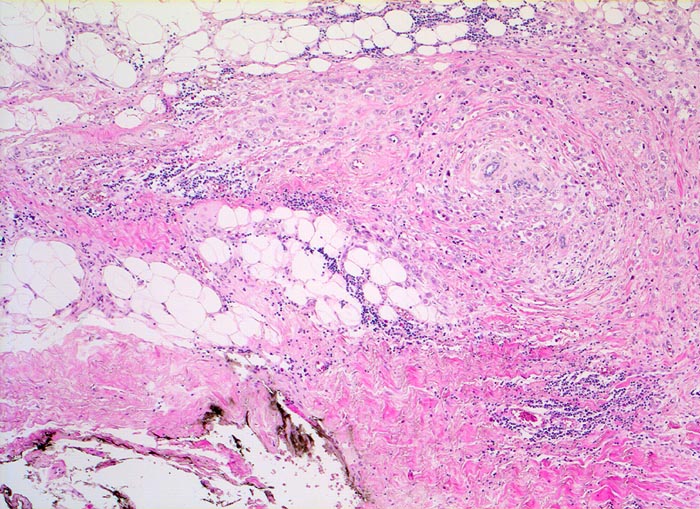

Morphologische Merkmale:

• Multifokale Infiltrate eines invasiv lobulären Mammakarzinoms: Kleine monomorphe, zytoplasmaarme Tumorzellen bilden einreihige Ketten (gänsemarschartig = Indian files) oder sind konzentrisch um nicht neoplastische Drüsen angeordnet.

• Lobuläre Neoplasie (=nicht invasiver intralobulärer Karzinomanteil): Neben den zystisch erweiterten Drüsen finden sich Mammaläppchen, deren Azini teilweise leicht vergrössert sind durch Ansammlungen von atypischen Zellen mit vergrösserten Kernen und prominenten Nukleolen. Die Basalmembran der tumorbefallen Azini ist erhalten.

• Nich neoplastisches Mammaparenchym mit Fibrose, erweiterten Gängen ausgekleidet von metaplastischem apokrinem Epithel.